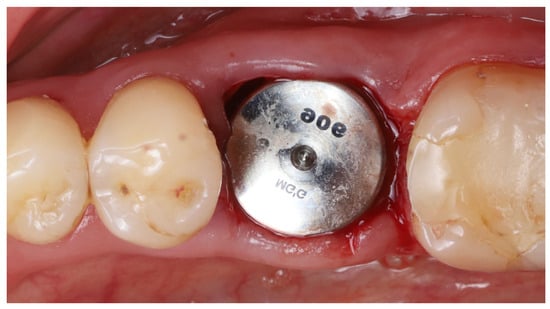

- Implant placement: A dental implant (Megagen Blue Diamond, 4.8 mm diameter × 10 mm length, conical “Deep thread” design) was inserted into the prepared osteotomy. The implant was centered within the socket, with its shoulder positioned roughly 5–6 mm below the level of the surrounding gingival margin (Figure 4). The implant fits snugly between the two buccal shields without exerting undue pressure on them. Primary stability was achieved; the implant had an insertion torque of about 35 N·cm, and verification with a resonance frequency analysis device showed an Implant Stability Quotient (ISQ) exceeding 70. (This high primary stability indicated that the implant was well stabilized in the septal bone despite the immediate placement.)

- Socket sealing with healing cap: The socket orifice was sealed with a large-diameter healing abutment instead of suturing a flap. A wide, 9 mm diameter, and 6 mm height standard healing cap was attached to the implant, which effectively covered the socket opening and conformed to the circumference of the socket (Figure 5). This approach is intended to protect the socket and support the surrounding gingival margins without requiring a flapped closure or graft. No additional bone graft or membrane was placed in the socket; a blood clot was allowed to fill the gaps between the implant and shields [17].